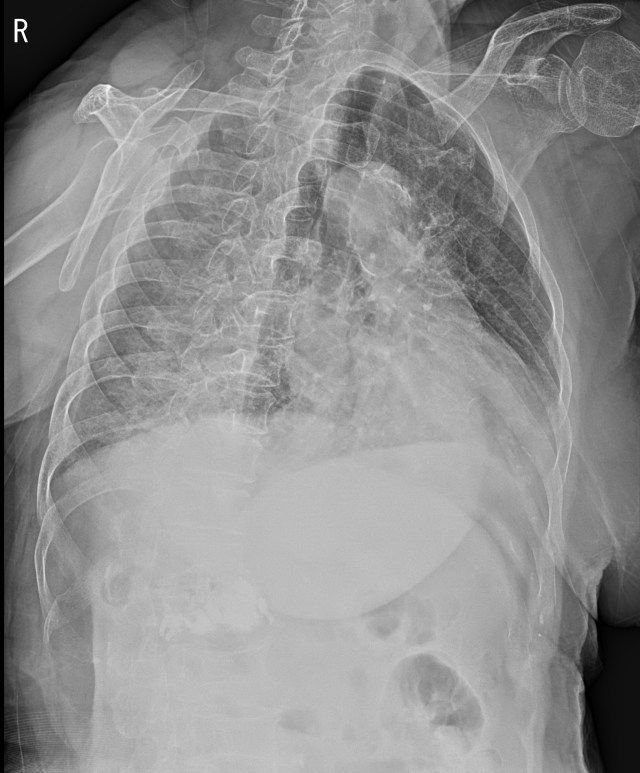

넘어진 과거력에 왼쪽 가슴에 통증이 있기에 늑골 골절의 가능성을 의심해서 Rib series를 촬영했습니다. 꼼꼼히 봐도 아무런 골절의심소견이 보이지 않습니다.

하지만, 환자분이 계속 통증이 심해지고 있다고 하시고, 뚜렷한 압통을 호소하고 계시기 때문에 흉벽 초음파를 실시했습니다.